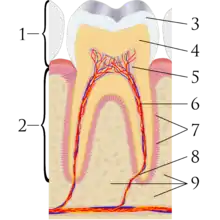

A tooth is composed of an outer shell of calcified hard tissues (from hardest to softest: enamel, dentin, and cementum), and an inner soft tissue core (the pulp system), which contains nerves and blood vessels. The visible parts of the teeth in the mouth – the crowns (covered by enamel) – are anchored into the bone by the roots (covered by cementum). Underneath the cementum and enamel layers, dentin forms the bulk of the tooth and surrounds the pulp system. The part of the pulp inside the crown is the pulp chamber, and the central soft tissue nutrient canals within each root are root canals, exiting through one or more holes at the root end (apical foramen/foramina). The periodontal ligament connects the roots to the bony socket. The gingiva covers the alveolar processes, the tooth-bearing arches of the jaws.[45]: 1–5